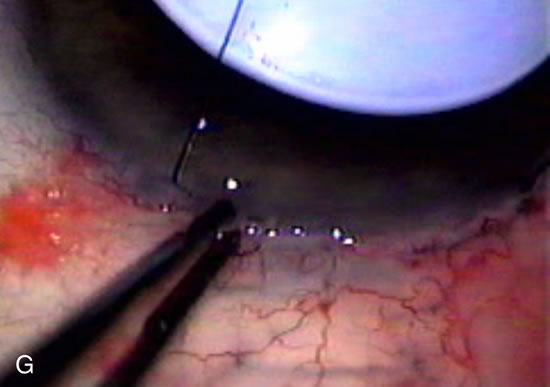

Fig. 7. Phacotrabeculectomy adjacent to a failed filter in cataractous eye. The ability to combine small-incision cataract extraction with trabeculectomy all through the same incision adjacent to the failed filter allows the surgeon to work in a familiar superior area. Avoiding incisions into the existing bleb decreases conjunctival buttonholes, hypotony, operating room time, and subconjunctival bleeding. A. Appearance of failed bleb with exposure of superior temporal quadrant gained with a corneal traction suture. B. Prepare a limbus-based conjunctival flap and a scleral flap. C. This bleb is at high risk to fail again justifying the need for MMC, 0.2 mg/cc applied on a pledget for 4 minutes. D. Insert the keratome and perform phacotrabeculectomy in the usual fashion.